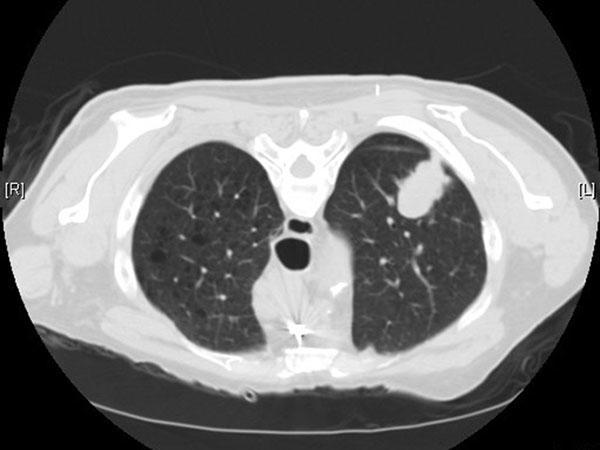

Nốt phổi là gì? Nguy cơ ác tính và lộ trình theo dõi an...

Giải thích nốt phổi dễ hiểu cho cộng đồng: phân loại đặc, kính mờ, bán đặc; nguy cơ ác tính theo kích thước và bờ; khi nào cần chụp PET CT, sinh...